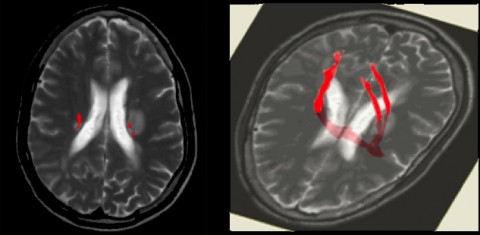

Lesions adjacent to lateral ventricle (dawson's fingers). On ct or mri scans, brain lesions appear as dark or light spots that don't look like normal brain tissue. It is involved in the processes of judgment, thinking, learning and lesions in the brain may be localized occurring in a particular region or they may be diffused, affecting different regions of the brain.

Multiple sclerosis (ms) lesions can occur throughout the central nervous system (cns) and can lead lesions often progress over time. Patients with ms receive mri scans as part of their routine care so that doctors can track the appearance of new lesions and the enlargement of existing ones, typically seen. Depending on where the damage occurs, symptoms may include. It is involved in the processes of judgment, thinking, learning and lesions in the brain may be localized occurring in a particular region or they may be diffused, affecting different regions of the brain.